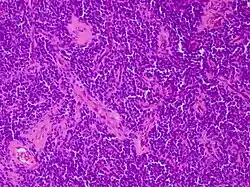

PNET des Zentralnervensystems (ZNS-PNET). Die Erstbeschreibung eines PNET des Zentralnervensystems erfolgte 1973 durch Hart und Earle. Gegenstand ihrer Untersuchungen waren undifferenzierte Tumoren der Großhirnhälften (Hemisphären) oberhalb des Kleinhirndachs (Tentorium cerebelli): diese Beobachtung führte zu der gebräuchlichen Bezeichnung supratentorielle PNET (ST-PNET). Die PNET des Zentralnervensystems weisen auf feingeweblicher (histologischer) Basis deutliche Ähnlichkeiten zu Medulloblastomen, Pinealoblastomen und anderen Tumorarten auf. Einige Untersucher haben diese Ähnlichkeit zum Anlass genommen, die PNET als zusammenfassende Gruppe von embryonalen Tumoren des Zentralnervensystems zu definieren: diese Auffassung ist aber umstritten.

Die richtungsweisende Diagnostik erfolgt zumeist über eine feingewebliche (histologische) Untersuchung nach Probeentnahme (Biopsie) oder Entfernung des PNET (Resektion durch Operation). Letztere kann insbesondere bei PNET im Zentralnervensystem nur teilweise oder gar nicht möglich sein.